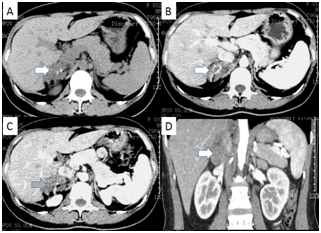

A 32 age women underwent a regular routine test 1 month ago that ultrasound showed a mass in the right adrenal gland. She denied any known medical conditions, such as hyperaldosteronism, hypertension and hypercortisolism. Further examination was taken in our hospital. The contrast-enhanced CT identified a quasi-circular nodular lesion in the right adrenal gland, measuring 6x6.5cm and displaying heterogeneous with mottling and spotty dense calcification on the edge of the mass. The margin of lesion was clear and presented 46 HU in plain scan and 68-113 HU in the enhancement. The tumor surrounded the right renal vein and part of postcava, but didn’t narrow the vessels (Figure 1). All of functional laboratory evolution showed negative including blood testing for catecholamines (epinephrine and norepinephrine) and their metabolites (metanephrine in serum and VMA in a 24-hour urine sample), free cortisol and ACTH (adrenocorticotropic hormone) in serum and plasma testing for renin-angiotensin-aldosterone under recumbent and upright state. A laparoscopic right adrenalectomy was performed (Figure 2) and postoperative pathology revealed a right ganglioneuroma. Immunohistochemistry showed S-100, CD56, Syn and CgA staining are positive Figure 3 & 4). After one year follow-up, the patient has not had any local recurrence and distant metastasis.

Figure 1 Angio Computed Tomography (CT): The arrows show a nodular lesion of the right adrenal gland with 6.5X6 cm surrounded right renal vein and part of postcava. (A) Plain scan (B) Arterial phase (C) Delay scan (D) Three-Dimension reconstruction.